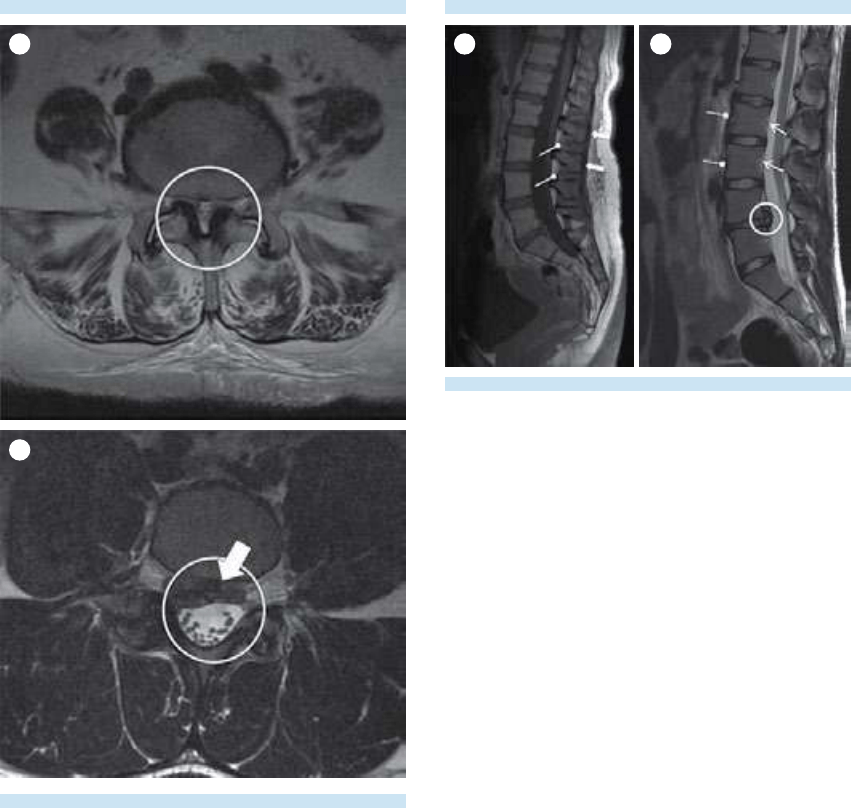

6. Evaluación de músculos paravertebrales,

tejidos blandos y hallazgos incidentales.